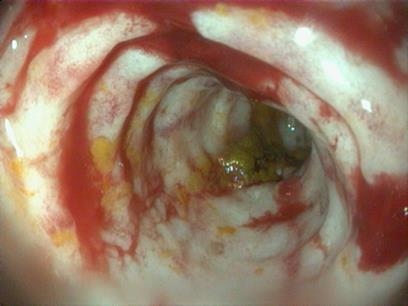

Colonoscopie/Duodenoscopie

Zowel het eerste deel van de dunne darmen als het laatste deel van de dikke darm kunnen in beeld gebracht worden. Hierdoor is het mogelijk om een correcte diagnose te stellen bij patiënten met chronische darmproblemen zoals diarree, persen en vermageren.

Voorbeeld 8. Colonoscopie: Chronische darmontsteking